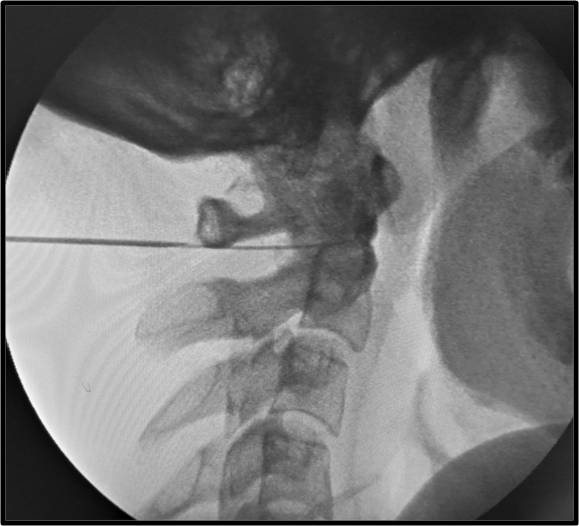

Τι είναι οι εγχύσεις στις αρθρώσεις της ανώτερης αυχενικής μοίρας της σπονδυλικής στήλης

Πρόκειται για την έγχυση μικρής ποσότητας στεροειδούς στην ατλαντοϊνιακή ή στην ατλαντοαξονική άρθρωση της ανώτερης αυχενικής μοίρας κάτω από ακτινοσκοπική καθοδήγηση. Η ανάπτυξη αρθρίτιδας ή ο τραυματισμός των αρθρώσεων αυτών μπορεί να αποτελεί πηγή χρόνιου σοβαρού πόνου στην αυχενοϊνιακή χώρα.